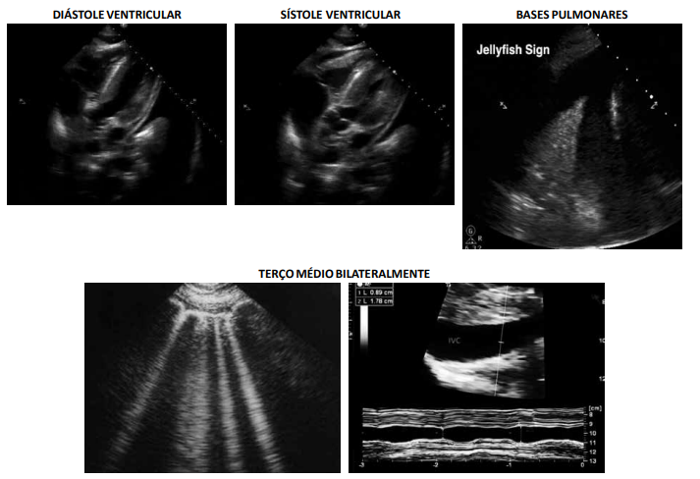

Uma paciente de 55 anos de idade, hipertensa, diabética e tabagista, foi ao pronto-socorro com dispneia, edema de

membros inferiores, estase jugular e estertores bibasais. O quadro iniciou-se junto com disúria, polaciúria e dor lombar, há

três dias. Na admissão: FC de 122 bpm; PA de 83 x 44 mmHg; FR de 24 irpm; sat. a 89 % em ar ambiente; TEC de 4 segundos;

temperatura 38,7 °C; e Giordano positivo à direita.

Com base na situação hipotética apresentada e nas imagens resultantes da realização do POCUS, assinale a alternativa correta.